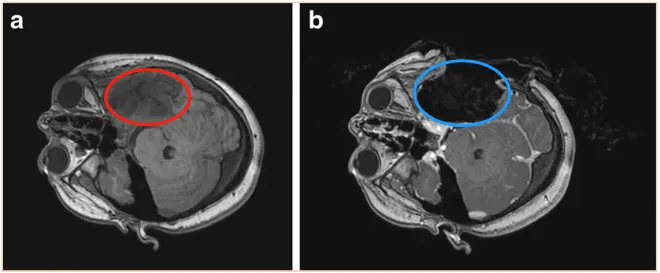

病例一:复发性左颞顶叶少突星形细胞瘤

一名11岁女孩,有头痛及癫痫反复发作病史。5年前发现左颞顶叶占位,并接受了部分切除手术,术后病理诊断为左颞顶叶少突星形胶质细胞瘤(WHO 2级)。如今肿瘤复发(下图a),需要进行二次手术。患者转诊至INC国际神经外科教授处,在术中神经电生理监测下,于配备术中磁共振成像(iMRI)的手术室内,采用神经导航引导方法实施了手术。术中MRI与术前影像对比证实肿瘤获得全切(下图b)。患者术后3年随访未见复发。

图:复发性左颞顶叶少突星形细胞瘤(WHO 2级)的术前MRI。b术中MRI显示病变已得到全切。